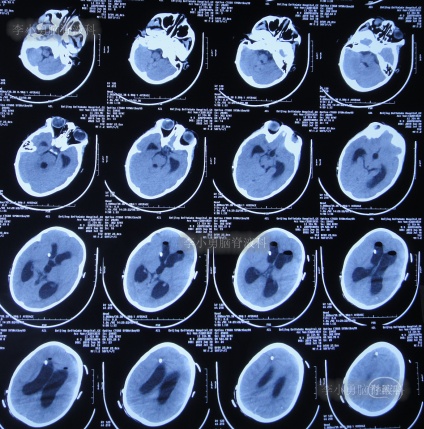

第3家医院治疗16天即2022年6月9日,不但依然发热,而且查头颅CT示脑室稍扩张(图-3)。

图-3:2022年6月9日头颅核磁